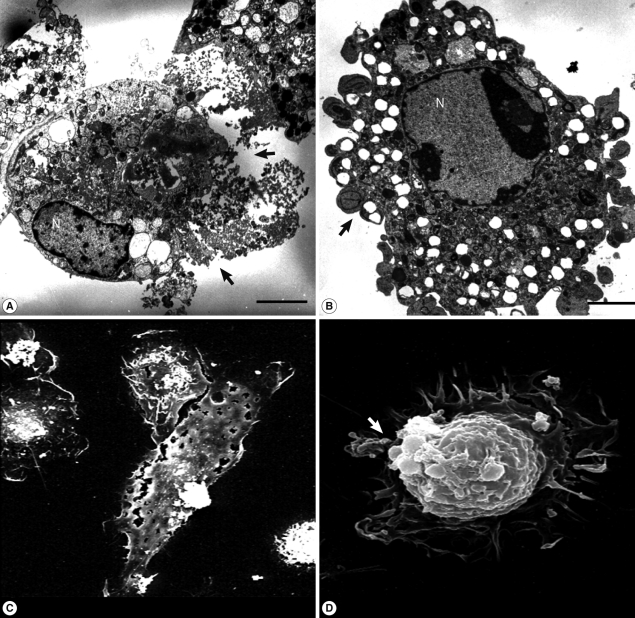

Fig. 2

TEM and SEM images of microglia treated with N. fowleri lysate. Microglial cells were treated with N. fowleri lysate (1 mg/ml) for 12 hr. Necrosis could be observed concomitantly with plasma membrane lysis (arrows; A, C), and programmed cell death with accompanying changes, including apoptotic bodies (arrows) and nuclear chromatin condensation (B, D). Bar=5 µm.

N. fowleri lysate (1 mg/ml) exerted severe morphological changes, including disruption and breakdown of the plasma membrane on the rat microglia, and significantly promoted cell death (Fig. 1). These effects were dose-dependent (Fig. 1). Microglial lethality was almost complete within 6 hr culture with N. fowleri lysate, generally appearing necrotic in nature and characterized by membrane swelling and lysis of the nuclear membrane and nucleus (Fig. 2A, 2C). Some microglial cells additionally evinced hallmarks of apoptosis, such as blebbing, formation of apoptotic bodies, and nuclear chromatin condensation (Fig. 2B, 2D). In previous reports, pathogenic Acanthamoeba culbertsoni lysate induced cytopathic effects, including necrosis and apoptosis, in primary rat microglial cells [21,22], suggesting that N. fowleri contact-independent cytotoxicity proceeds similarly.